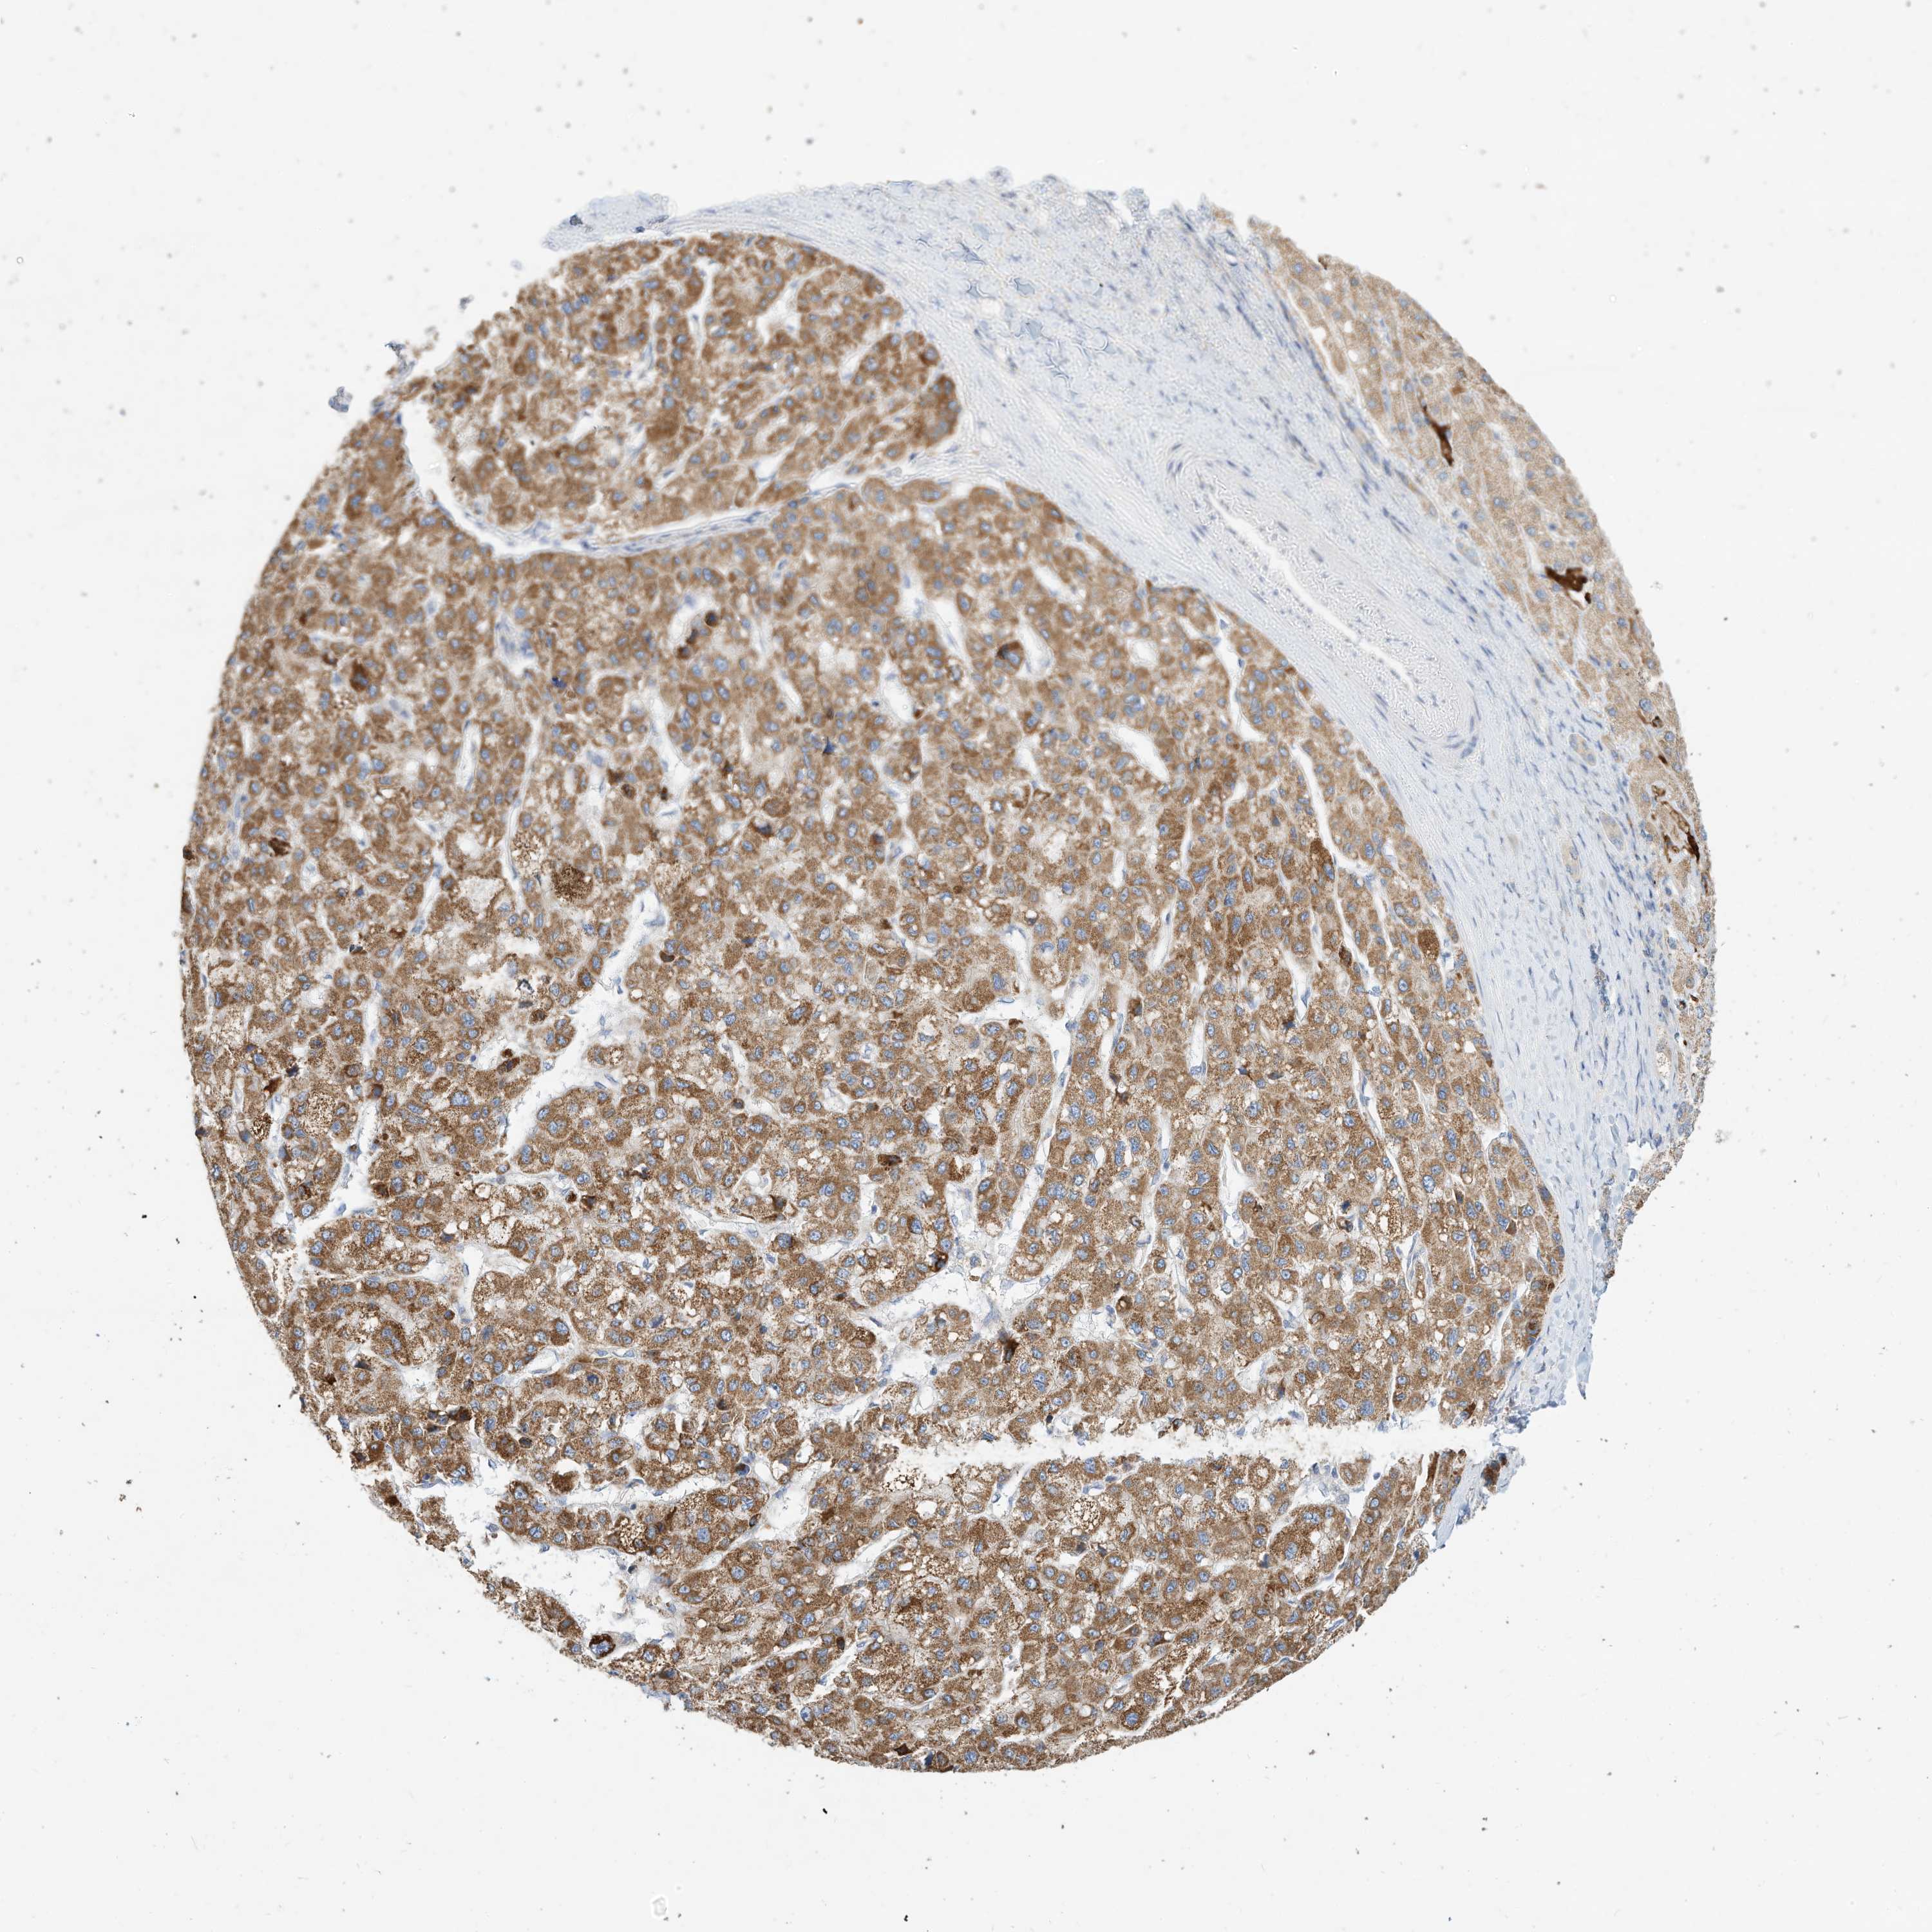

LIVER CANCER - Protein expressioni

A mouse-over function shows sample information and annotation data. Click on an image to view it in a full screen mode. Samples can be filtered based on level of antibody staining by selecting one or several of the following categories: high, medium, low and not detected. The assay and annotation is described here.

Note that samples used for immunohistochemistry by the Human Protein Atlas do not correspond to samples in the TCGA dataset.

Antibody stainingi

Antibody staining in the annotated cell types in the current human tissue is reported as not detected, low, medium, or high, based on conventional immunohistochemistry profiling in selected tissues. This score is based on the combination of the staining intensity and fraction of stained cells.

Each image is clickable and will lead to virtual microscopy that enables deeper exploration of all samples and also displays staining intensity scores, fraction scores and subcellular localization as well as patient and tissue information for each sample.

Antibody HPA030345

Staining

High

Medium

Low

Not detected

Intensity

Strong

Moderate

Weak

Negative

Quantity

>75%

75%-25%

<25%

None

Location

Nuclear

Cytoplasmic/membranous

Cytoplasmic/membranous,nuclear

Cholangiocarcinoma

Carcinoma, Hepatocellular, NOS